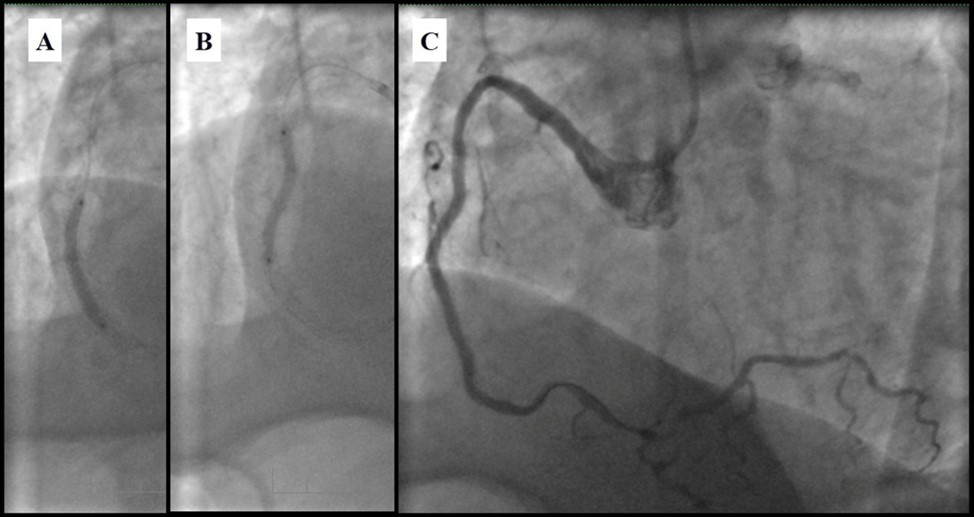

Angiography revealed rare anatomical variation LMCA quadrifurcation (Figure 1, Figure 2), 50% stenosis of the distal part of the LMCA, 40% stenosis of the ostial segment of left anterior descending (LAD) artery and diffuse prolonged 70-75-95% stenosis in mid-segment (Figure 3), 75% stenosis of the ostial segment of the circumflex (CX) artery, 75% stenosis of the ostial segment of the first marginal branch (OM1), 75-90% stenosis of the proximal segment of the intermediate artery (IMA), prolonged diffuse severe 90-95% stenosis of mid-segment of the right coronary artery (RCA) (Figure 4).

Figure 1.Quadrifurcation of the left main coronary artery

Quadrifurcation of the left main coronary artery

Figure 3.Prolonged diffuse severe 90-95% stenosis of mid-segment of the right coronary artery. A - Left anterior oblique 45° projection; B – Right anterior oblique 45° projection.

Prolonged diffuse severe 90-95% stenosis of mid-segment of the right coronary artery.               A - Left anterior oblique 45° projection; B – Right anterior oblique 45° projection.

Figure 4.A - 50% stenosis of the distal segment of the LMCA; B - 70-75-95% stenosis in mid-segment of the LAD.

A - 50% stenosis of the distal segment of the LMCA; B - 70-75-95% stenosis in mid-segment of the LAD.